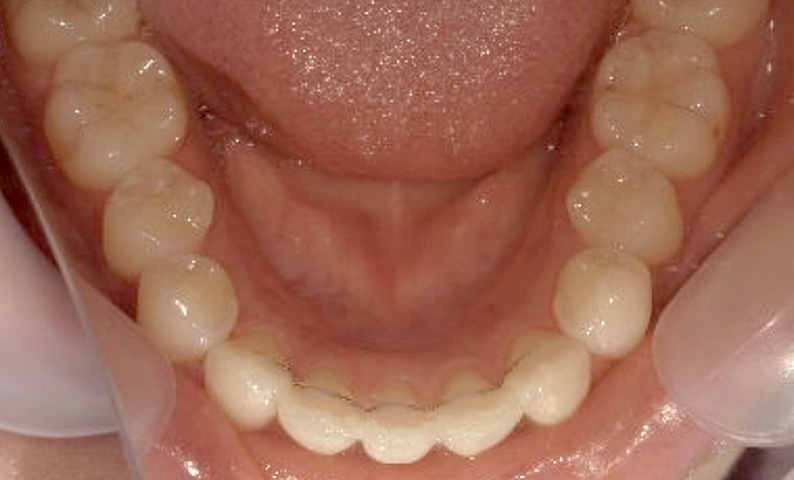

症例_023 上下顎の部分矯正

治療期間:11ヶ月金額:45万円+税女性前歯のガタガタ八重歯